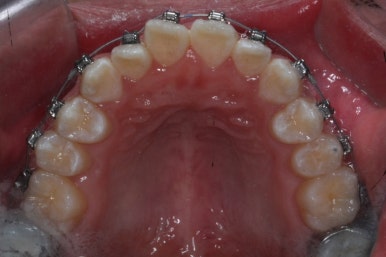

수술 후 6주가 지나고, 수술 후 교정과정에 들어갑니다.

수술 전 교정과정이 이미 많이 진행 되었기 때문에 디테일한 맞물림과 치아배열 정리만 해주면 치료를 종료할 수 있겠습니다.